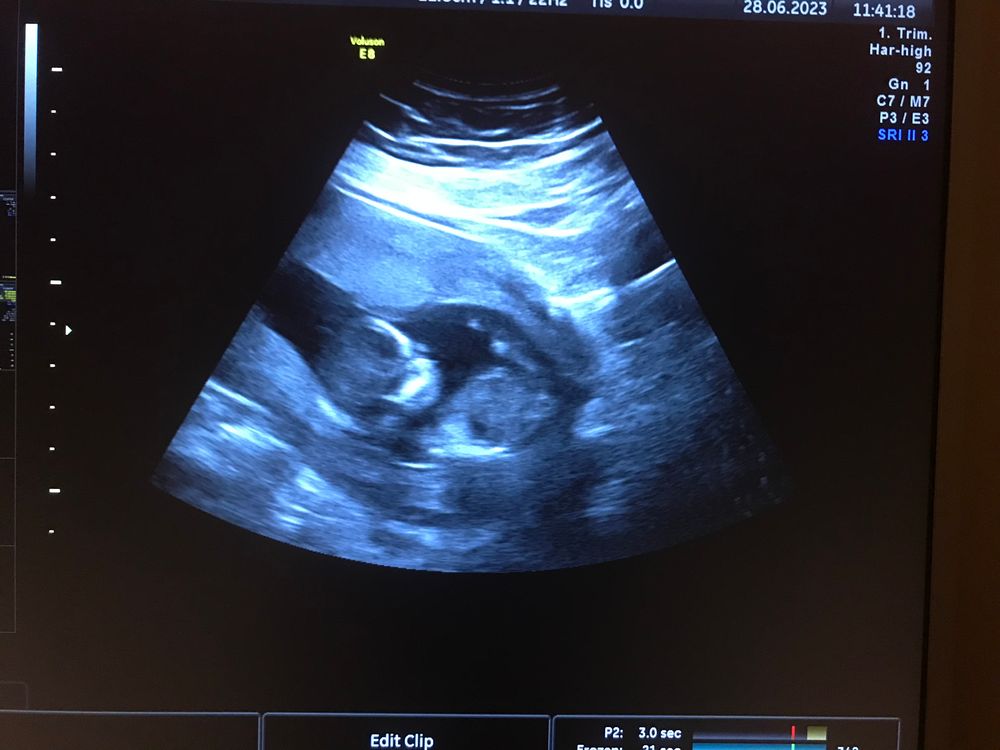

15 недель.

14.5 первый скрининг прошла, все хорошо. Начала пить кардиомагнил 150 (преэклампсия) и кальций 1 г вечером + давно пью витамины+допигит. Токсикоз иногда передает привет🤷‍♀️. По узи поставили локальный тонус, хотя я его не чувствую. Живот не болит, не тянет и не каменеет. В понедельник иду на прием и конечно жду результаты крови, надеюсь что там все хорошо 🙏(Сказали 10 дней где то). Грудь так же и болит. Пока что все 🤷‍♀️😅.